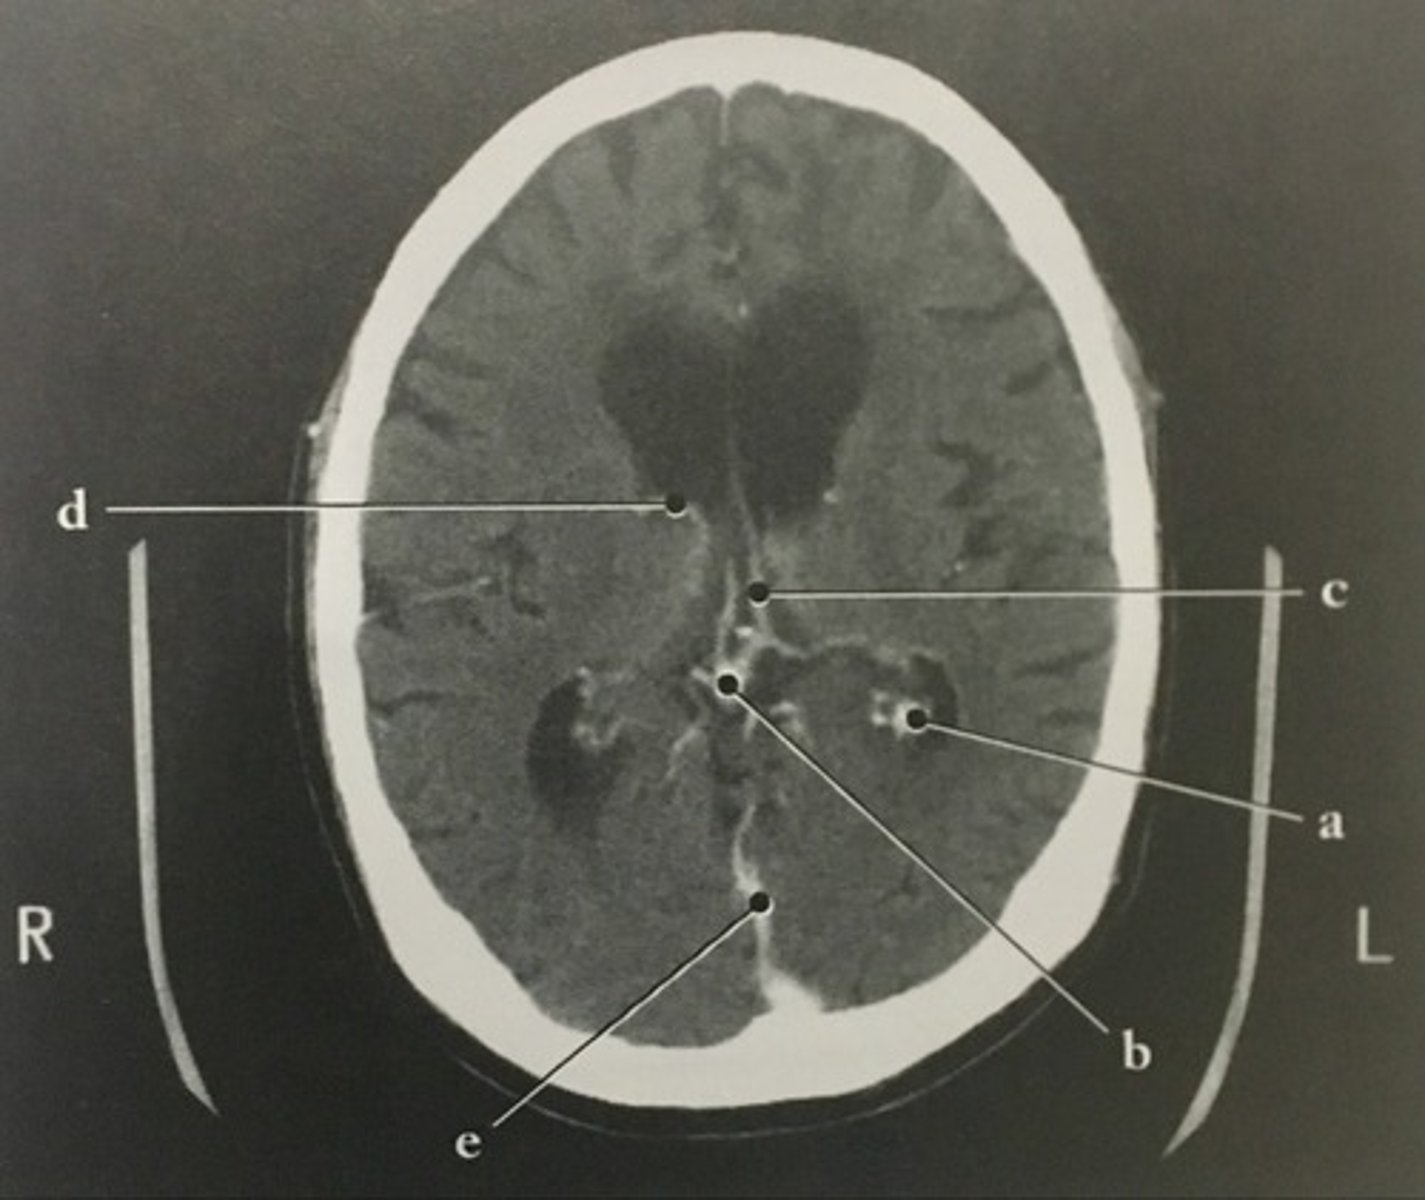

Vein of Galen

Identify structure B on this axial CT slice of the brain.

<p>Identify structure B on this axial CT slice of the brain.</p>

Internal cerebral veins

Identify structure C on this axial CT slice of the brain.

<p>Identify structure C on this axial CT slice of the brain.</p>

Thalamostriate vein

Identify structure D on this axial CT slice of the brain.

<p>Identify structure D on this axial CT slice of the brain.</p>

Straight sinus

Identify structure E on this axial CT slice of the brain.

<p>Identify structure E on this axial CT slice of the brain.</p>